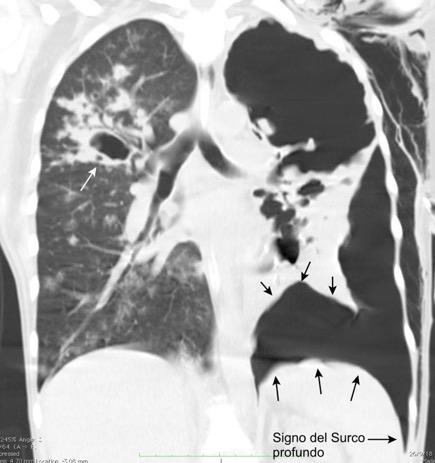

Diafragma “colgante” (“dangling sign”)

(“Dangling sign”)

TC. Mejor con multicorte. (reconstrucciones).

Asociación: Aire en pared.

Fracturas costal .Rotura esplénica. Neumoperitoneo.

Diafragma discontinúo Herniación de la grasa omental

Desser TS et al.The dangling diaphragm sign: sensitivity and comparison with existing CT signs of blunt traumatic diaphragmatic rupture. Emerg Radiol 2010